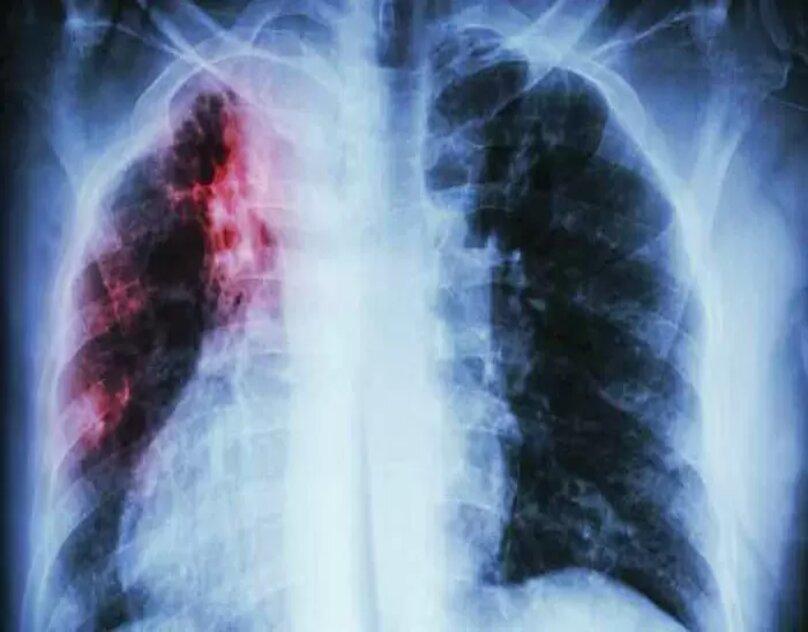

Interstitial Lung Disease encompasses a spectrum of disorders characterized by progressive scarring of lung tissue. This scarring impairs lung function, compromising the body's ability to oxygenate the bloodstream effectively. Dr. Parthiv Shah, a leading Lung Specialist in Mumbai, offers comprehensive treatment for all forms of ILD, extending a lifeline to those in need.

Diagnosing ILD requires a comprehensive evaluation, including blood tests, imaging studies like CT scans, and pulmonary function tests. Dr. Parthiv Shah employs a meticulous approach to pinpointing the underlying cause of ILD, ensuring accurate diagnosis and tailored treatment plans.